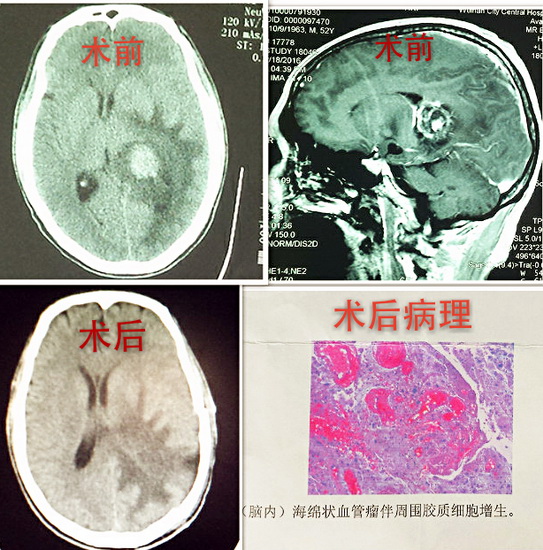

患者吕某,男,52岁,渭南华州区人, 患者入院时自诉头痛12天,入院后行检查颅脑CT提示:左侧侧脑室后脚占位,周围伴水肿。入院诊断为左侧侧脑室占位性病变。我市神经外科首席专家白西民主任医师高度重视,积极进行术前准备,在赵云洁住院医师的配合下在全麻下行左侧侧脑室肿瘤切除术,手术顺利。术后病理报告为:脑深部海绵状血管瘤伴胶质增生。患者术后头痛好转,无神经功能障碍。

脑内海绵状血管瘤也称海绵状血管畸形,或称海绵状瘤,多伴有癫痫、出血和局部神经功能缺损症状。此患者肿瘤位于侧脑室,位置较深,且毗邻重要结构,手术路径长,周围脑组织水肿广泛,颅内压高,手术难度较大,因此,手术者必须有扎实的神经外科解剖知识、熟练的显微外科技术。本例手术在神经外科二病区医务人员的努力下成功切除肿瘤,患者没有神经功能缺损,效果良好。